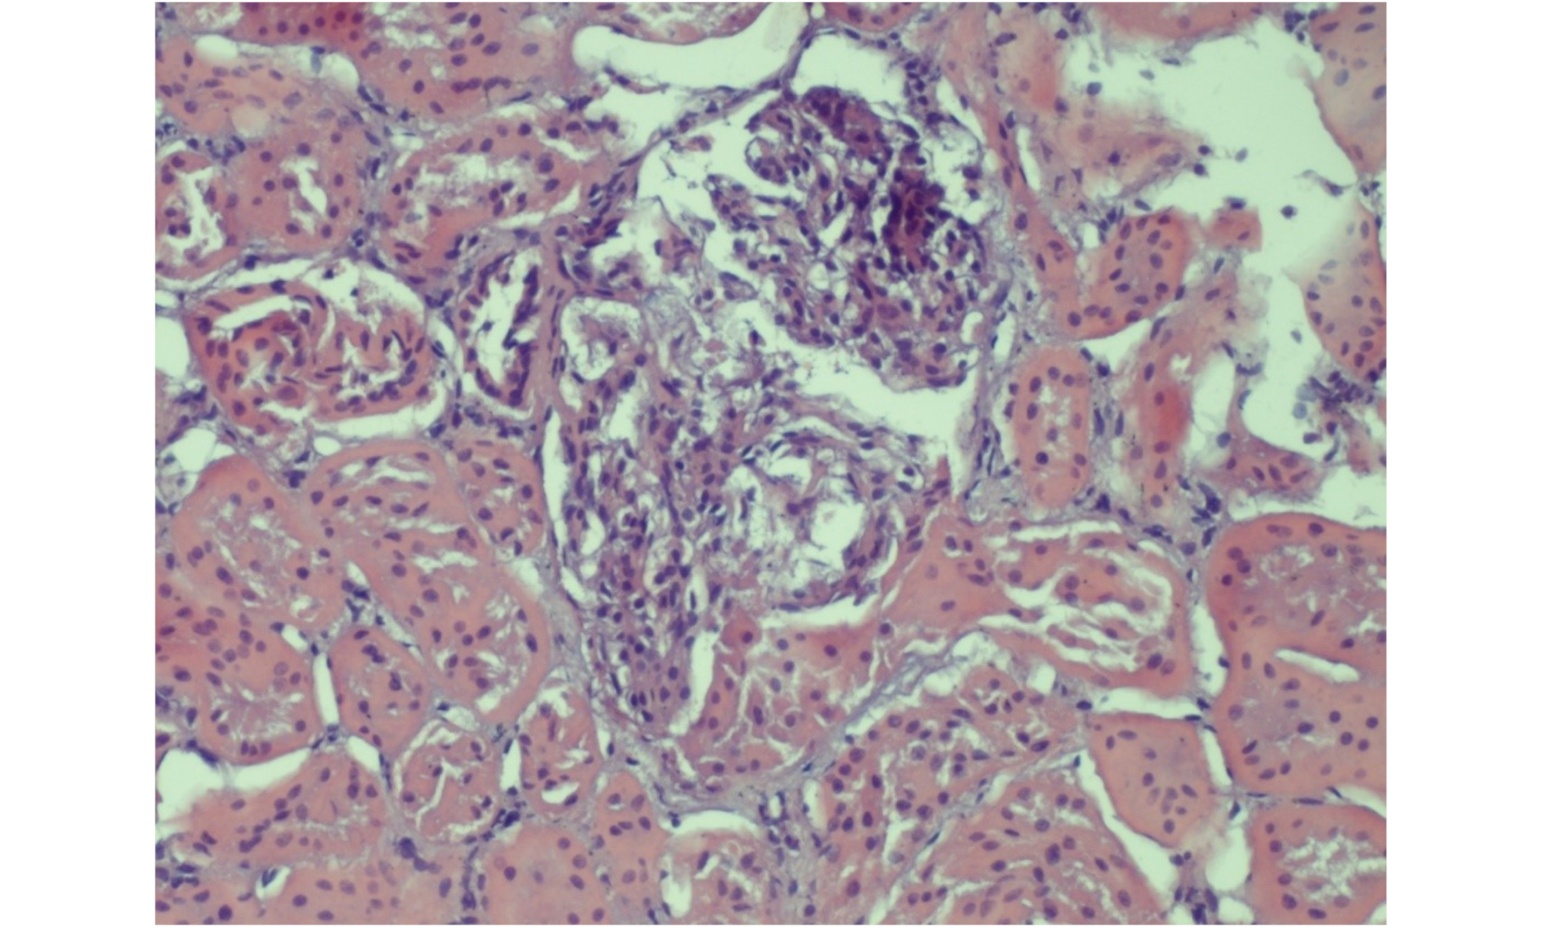

Histological lesions were observed in 19 kidney samples, all exclusively from group 1, with cadmium concentrations > 5.72 mg/kg w/w and from animals aged between 50 and 60 months. These samples exhibited the presence of neutrophils within the glomerular tufts and varying degrees of mesangial cell proliferation. Features consistent with obstruction typical of acute nephritic syndrome—progressing toward chronicity—were also observed. The glomerular capillary lumens appeared reduced, thereby compromising glomerular filtration (Figure 1).

Figure. 1. Kidney: obstruction of glomerular capillary lumina. HE (Hematoxilin Eosin) x 40.